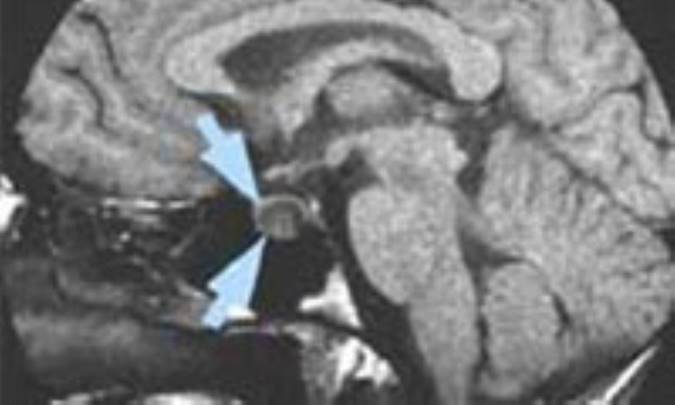

بررسي‌هاي‌ تشخيصي‌ ممكن‌ است‌ شامل‌ آزمايش‌هاي‌ مايع‌ مغزي‌ نخاعي‌ و خون‌، راديوگرافي‌ جمجمه‌، سي‌تي‌اسكن‌ يا ام‌آرآي‌ مغز، آنژيوگرافي‌ و بررسي‌هاي‌ بينايي‌ باشد.